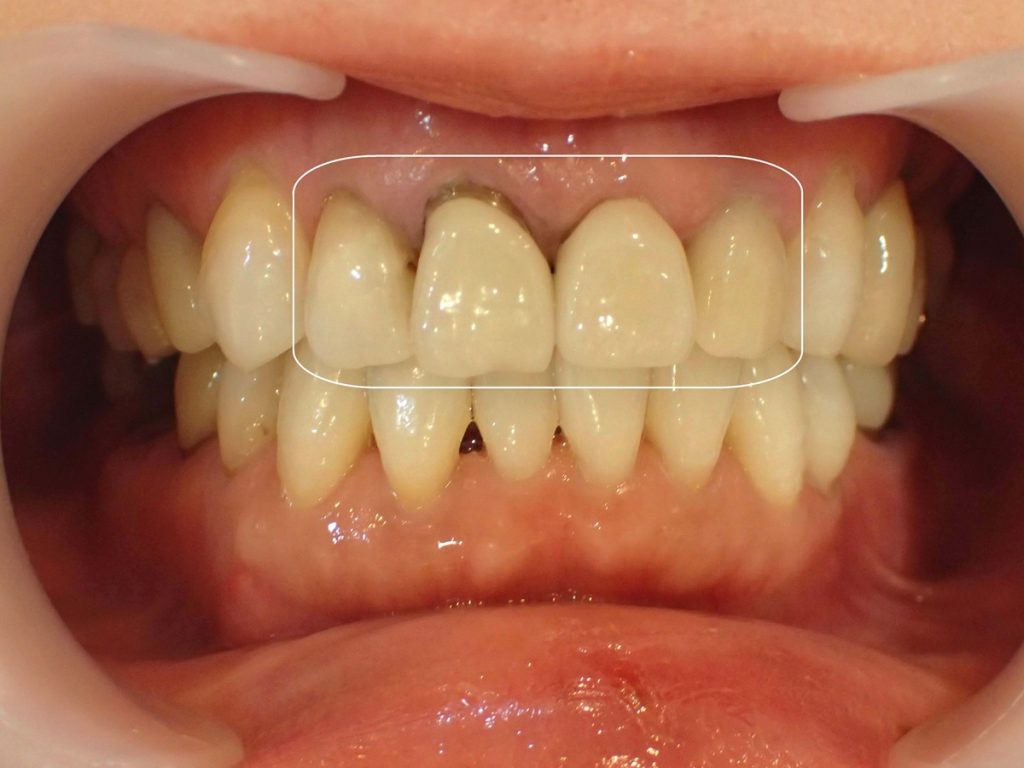

【ブラックマージン治療前】

【ブラックマージン治療後】

治療期間:1カ月半

通院回数:4回

治療内容:セラミック矯正3本

前歯3本にセラミック治療を行った方の症例です。

まわりの天然歯と比べて差し歯が黄色く変色し、歯茎部分が黒くなっていました。

セラミック治療によりまわりの歯と比べても変わらない透明感と厚みの状態にし、ブラックマージン(歯茎の黒ずみ)も改善しました。

当院では土台部分も含めて金属を一切使用しないため、時間が経って歯茎が再び黒ずむ心配がありません。